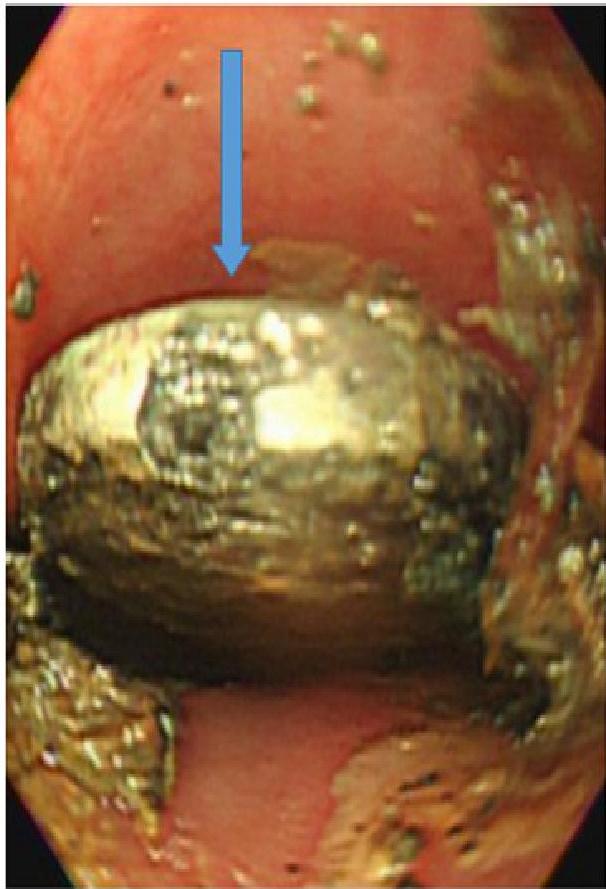

The “Button Battery” Emergency Risk

- Risks: Esophageal burns, fistula formation (tracheoesophageal), hemorrhage.

- X-Ray Sign: “Double Halo” or “Step-off” sign on lateral view.

- Action: Immediate removal required if stuck in the esophagus.

A, B, C: Imaging examples of button battery ingestion.